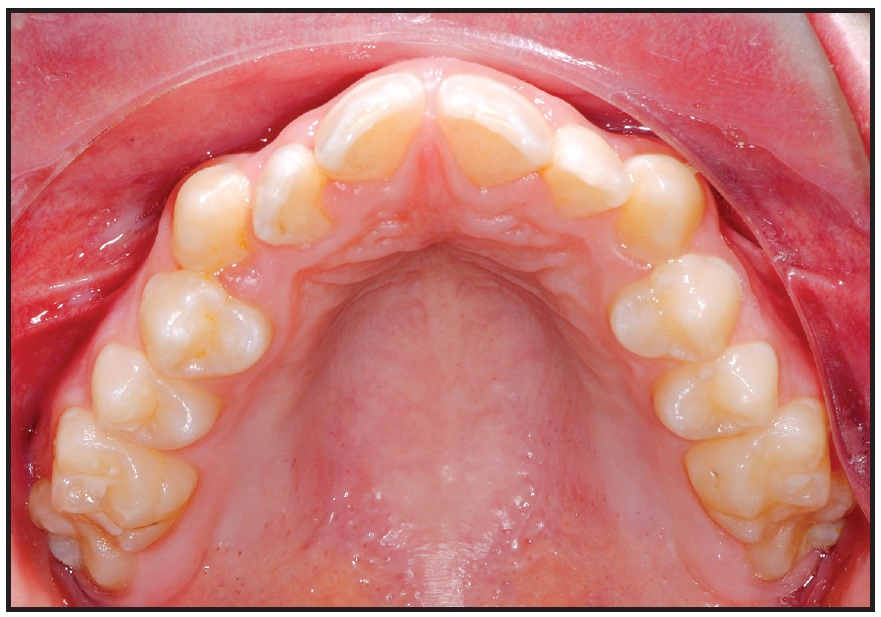

The patient was instructed to turn the expander .2mm per day. Five days after the initial activation, two additional 90° turns were performed to assess the mobility of the maxillary halves. After 27 days, about 6mm of expansion had been achieved (Fig. 8). The expander was left passively in place for 10 months to maintain the expansion during orthodontic treatment with a fixed appliance.

Fig. 8 Case 2. A. Insertion of TADs. B. Before and after 27 days of expansion.